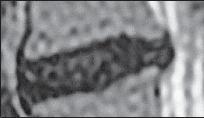

МРТ № 5

На МРТ № 5 наблюдается межпозвонковый диск на более поздней стадии развития дегенеративно-дистрофического процесса.